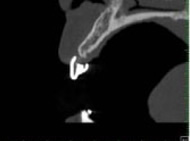

先程のX線診査に加えて、CTスキャンを行なうことにより、3次元的な骨の状態を把握できます。断層撮影ですので、術前に立体的な骨量、骨密度、神経や血管の位置がわかり、術中のトラブルをなくします。また、理想的なインプラントの埋入ポジションに充分な骨がない場合は、骨を造ってから行ないます。